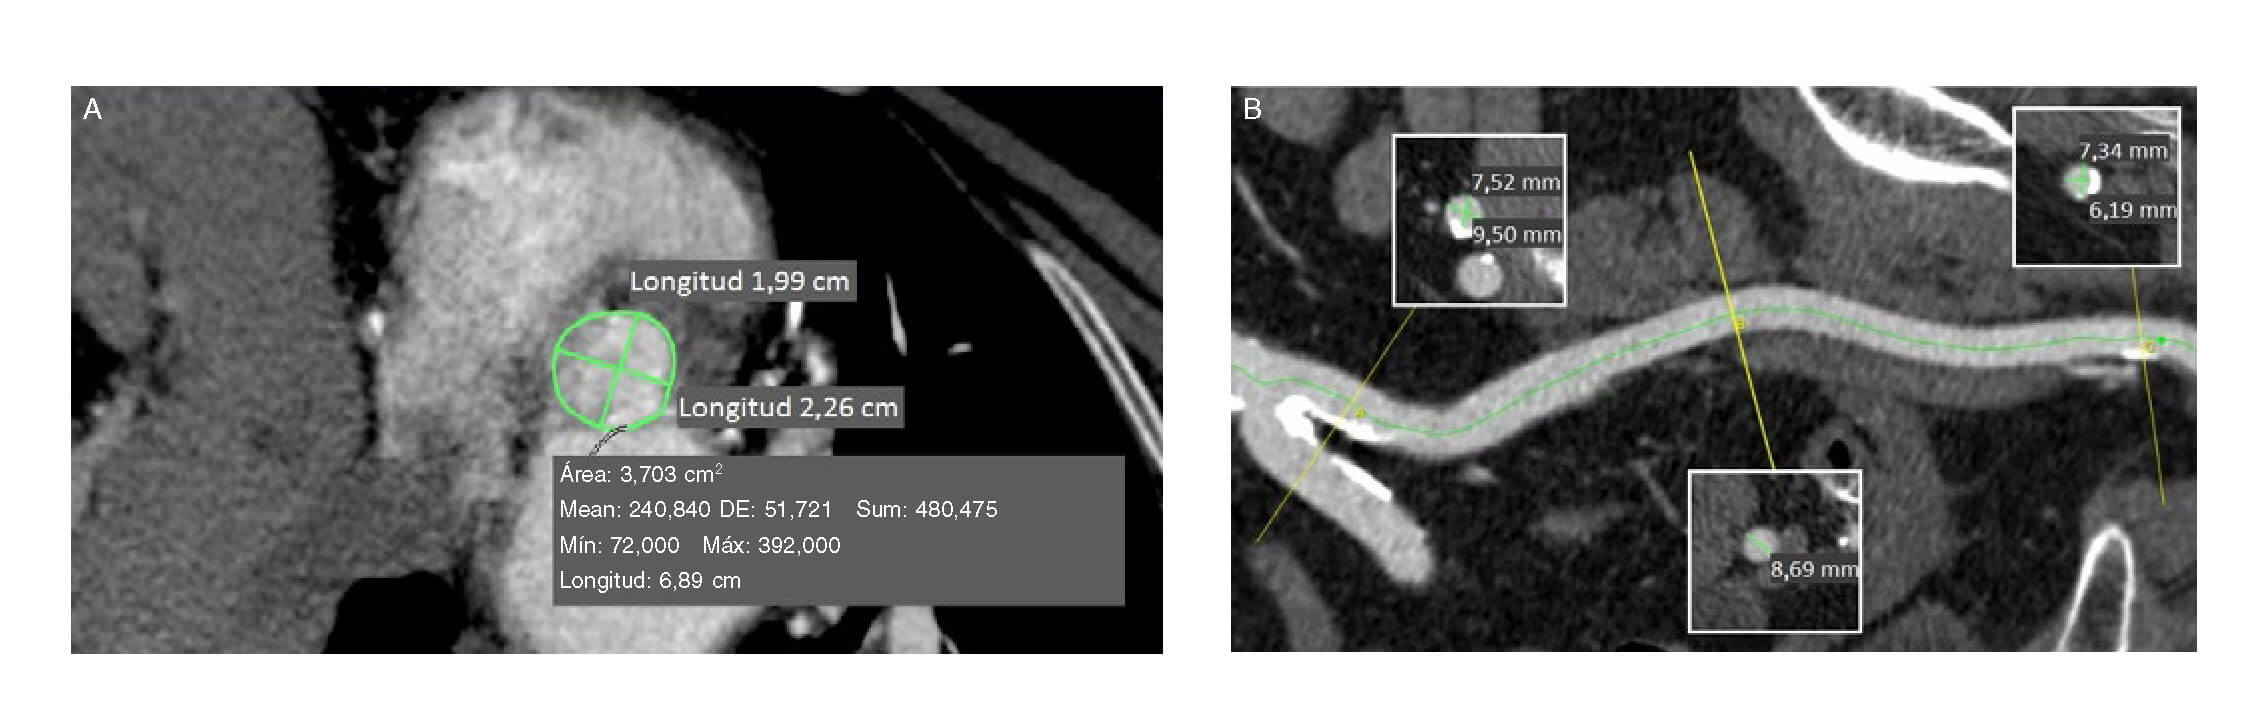

Se valoró por el equipo multidisciplinario y, considerando su edad y su alto riesgo quirúrgico, se rechazó para tratamiento quirúrgico. Se completó el estudio mediante angiotomografía computarizada, que mostró que la paciente era apta para realizar un implante percutáneo de válvula aórtica (TAVI) transfemoral (figura 1A, B).

Figura 1. Angiotomografía computarizada antes del procedimiento. A: medidas del anillo valvular aórtico: diámetro mínimo 1,99 cm, diámetro máximo 2,26 cm, perímetro 6,89 cm, área derivada del perímetro 3,70 cm2. B: medidas del eje ilíaco-femoral izquierdo: diámetro mínimo de la arteria femoral común 6,19 mm, diámetro mínimo de la arteria ilíaca externa 8,69 mm, diámetro mínimo de la arteria ilíaca primitiva 7,52 mm. Máx: máximo; Mean: media; Mín: mínimo; DE: desviación estándar; Sum: suma.